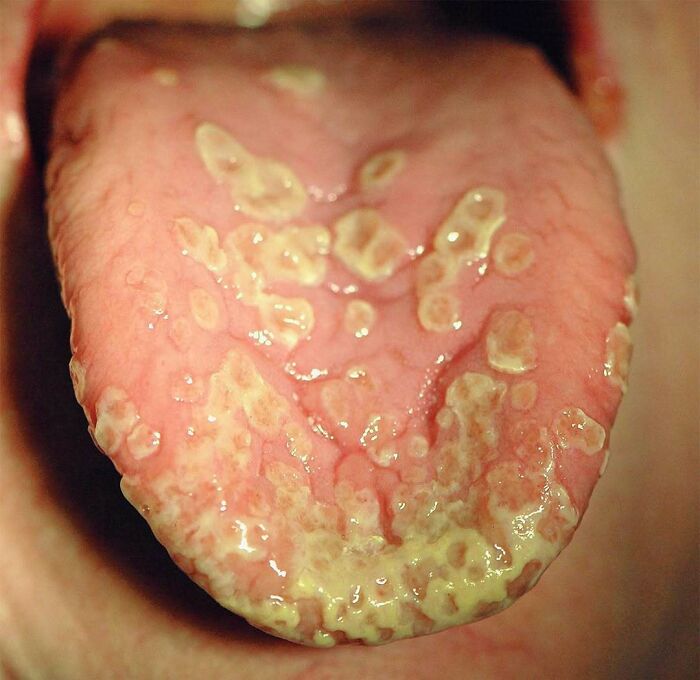

Strawberry tongue seen in scarlet fever.

Scarlet fever is an infectious disease resulting from a group A streptococcus (group A strep) infection, also known as Streptococcus pyogenes. The signs and symptoms include a sore throat, fever, headaches, swollen lymph nodes, and a characteristic rash. The rash is red and feels like sandpaper and the tongue may be red and bumpy. It most commonly affects children between five and 15 years of age.

Scarlet fever affects a small number of people who have strep throat or streptococcal skin infections. The bacteria are usually spread by people coughing or sneezing. It can also be spread when a person touches an object that has the bacteria on it and then touches their mouth or nose. The characteristic rash is due to the erythrogenic toxin, a substance produced by some types of the bacterium. The diagnosis is typically confirmed by culturing the throat.